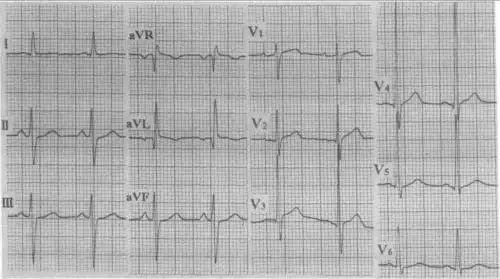

患者男,54岁,图为其常规体检心电图结论:窦性心律左前分支传导阻滞